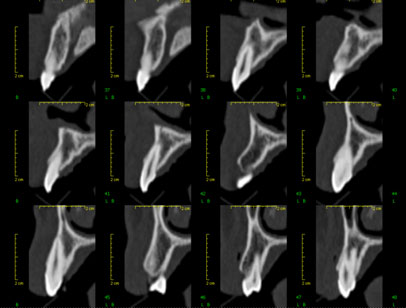

Este estudio dental genera reconstrucciones en múltiples planos de mandíbula, maxilar superior y piezas dentarias. Ofrece grandes ventajas con respecto a los estudios radiográficos dentales convencionales como la radiografía intraoral, la ortopantomografía y la cefalometría lateral.

- Ofrecer la posibilidad de reconstrucción multiplanar en 2D y en 3D

En el campo de la implantología, si la ortopantomografía obtenida previamente no es concluyente para valorar la viabilidad y las características del implante, el tac dental ofrece al odontólogo la mayor precisión de anatomía dentaria y de calidad del hueso subyacente, permitiendo así decidir la viabilidad, las dimensiones y la posición final del implante. Entre otros parámetros, el TC dental permite valorar aspectos fundamentales para el odontólogo en el estudio anterior al implante, como son:

- La calidad y cantidad de hueso disponible

- La anchura y altura de los arcos dentales

- La inclinación del contorno óseo

- La presencia de discontinuidades óseas

- Evidencias de anatomía atípica

- La presencia de patología

- La localización exacta de determinadas estructuras anatómicas, como por ejemplo, senos maxilares, canales mandibulares, agujeros mentonianos, agujeros mandibularesâ&